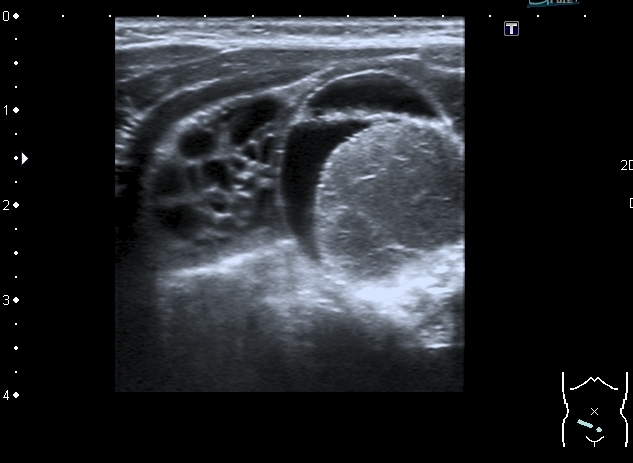

У девочки 5 месяцев ранее на УЗИ нашли образование в полости таза . С заключением киста яичника направлена к нам.

На УЗИ справа от мочевого пузыря - солидно - кистозное образование около 3 см. Образование прилежит к правому яичнику, который визуально не изменён, но смещается относительно его при движениях брюшной стенки Относительно яичника образование гиповаскулярное Выставил диагноз объёмного образования полости таза (дифференцировать энтерокистому и дермоид). Не думаю, что образование исходит из яичника, поэтому стартую тему в гастроэнтерологических исследованиях.